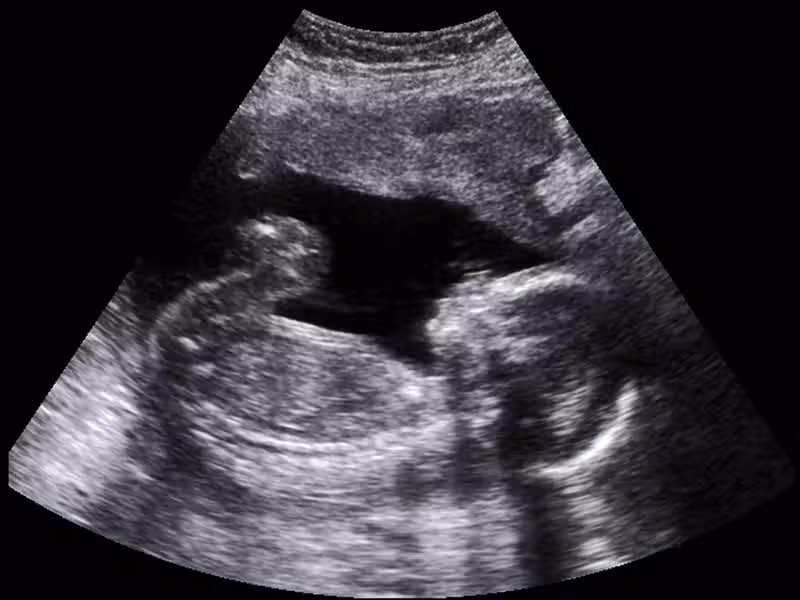

示意圖來源:女人樂生活、媽咪寶寶